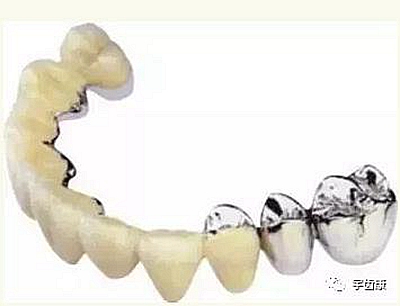

烤瓷牙結(jié)構(gòu)知識

烤瓷牙的設(shè)計方式